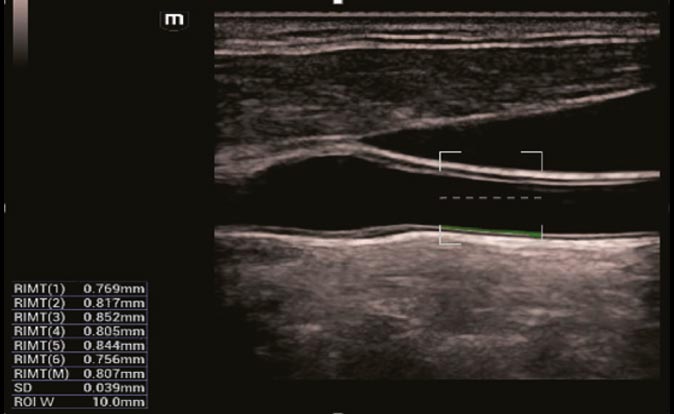

Evaluación de IMT con mayor precisión: RIMT

El IMT basado en datos de radiofrecuencia es independiente de la imagen y ofrece estadísticas de IMT automáticas y extremadamente precisas de 6 ciclos cardíacos en tiempo real.